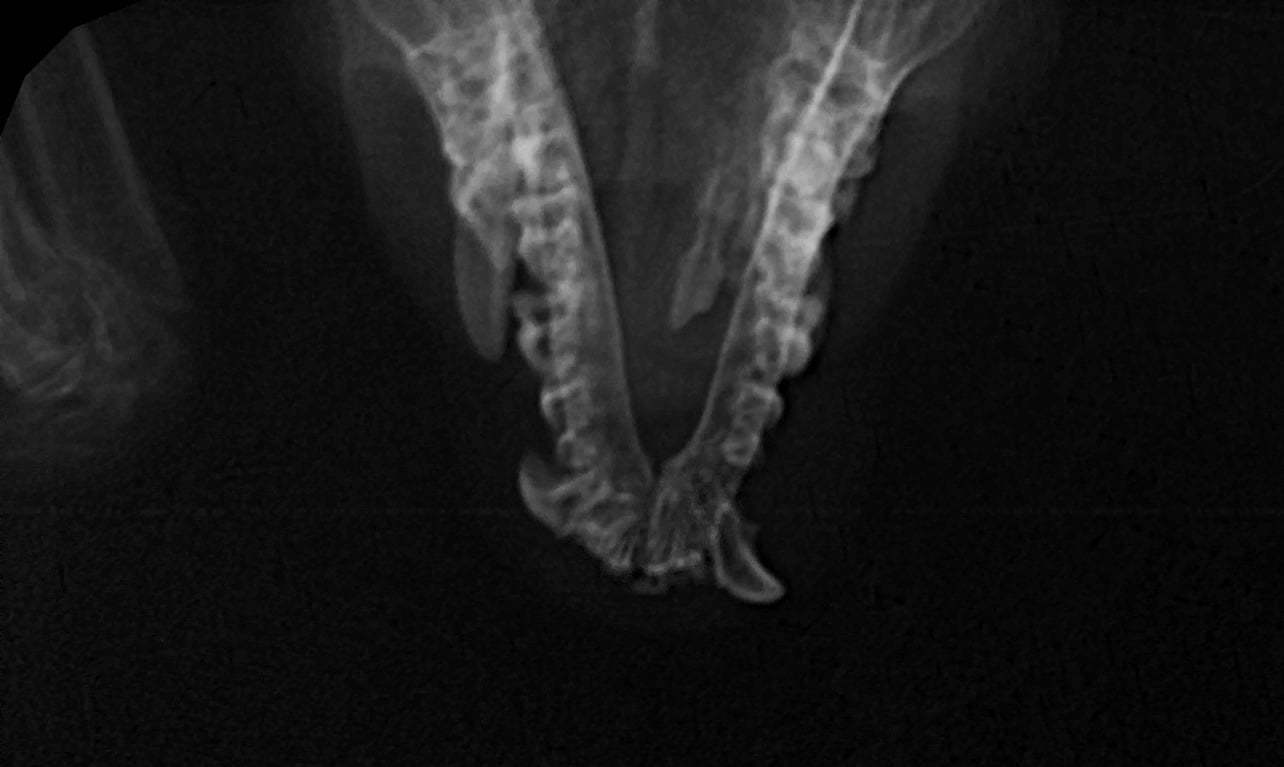

Нижний клык. Судя по цвету, по тому как он торчит, и как Бря плохо ест, стараясь выбрать именно мягкую еду - скорее всего болит. Видимо последствия травмы. На рентгене похоже на застарелый перелом челюсти

Ну и как обычно, потянешь за ниточку - получишь клубок: всплыли и другие проблемы. Помимо "зоопарка" снаружи и внутри - проблемы с крыльями. Пальцы целы, так что предварительно выпускная, а вот перепонки... Будем лечить. В пятницу (здравствуй снег и пробки 10 баллов) отвезли анализы в лабораторию, стоматологическая операция по плану назначена на воскресенье. Как обычно: не загадываем и действуем по обстоятельствам.

Кстати, на видео виден тот самый злополучный зуб.